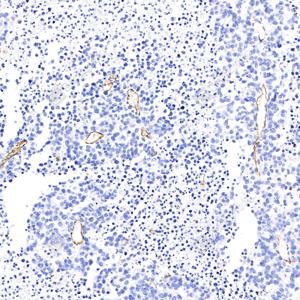

IHC检测CD34蛋白(货号 GB113798). 样品: 小鼠肺, 4%多聚甲醛 (货号G1101) 固定12-24小时. 抗原修复: 柠檬酸抗原修复液(干粉, pH 6.0) (G1201), 98℃, 20分钟. —抗: 1: 1000稀释, 4℃ 孵育过夜. 二抗: HRP标记山羊抗兔IgG (H+L) (货号GB23303), 1: 200稀释, 室温孵育1小时. |